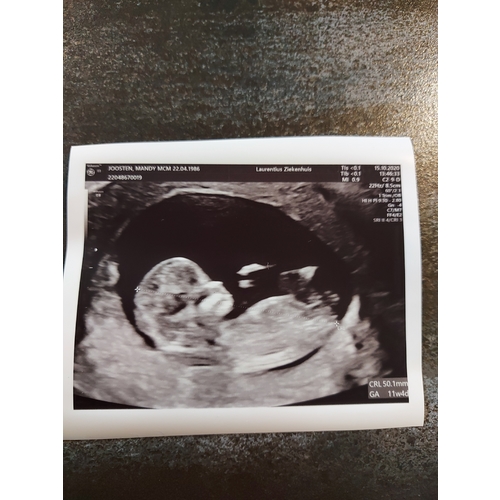

Dit was met precies 11 weken, je ziet echt al een heel mensje 💖